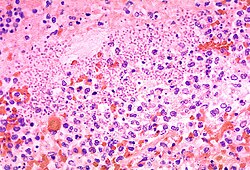

Die feingeweblichen Untersuchungen in der Medizin dienen verschiedenen Zwecken wie der Frühdiagnose von Tumoren (z. B. Magenbiopsie), Klassifizierung von Tumoren (gutartig/bösartig), Nachweis von Stoffwechselerkrankungen und parasitären, bakteriellen, entzündlichen Erkrankungen und der Hilfe zur Therapiewahl. Man spricht von morphologischer Diagnostik, da der Befund anhand des Erscheinungsbildes und des färberischen Verhaltens der Gewebestrukturen erstellt wird.

Eine erste Gewebelehre begründete in der Antike Aristoteles. Erasistratos baute diese Lehre aus und es wurde zwischen Gewebe und Parenchym unterschieden. Als Begründer der modernen Histologie gilt Xavier Bichat (1771–1802), der ohne das im 17. Jahrhundert bereits allgemein bekannte Mikroskop 21 Gewebetypen im menschlichen Körper beschrieb. Mit seiner Schrift Anatomie générale begründete er 1801 die allgemeine Gewebelehre, die sich mit in allen Organen vorkommenden Geweben befasst. Er verlegte den Sitz der Krankheiten aus den Organen in die Gewebe und folgerte, dass gleiche Gewebe in verschiedenen Organen gleichartig erkranken können.[2] Die Entstehung der Histopathologie schreibt man Johannes Müller zu, der 1838 ein Buch über die Natur und Struktureigenschaften von Krebs veröffentlichte. Als Vater der Histopathologie wird Rudolf Virchow (1821–1902) bezeichnet.